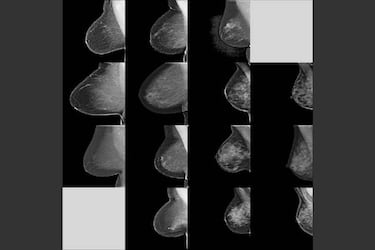

La densidad de la mama es el término que se usa para describir la cantidad de tejido denso en comparación con la cantidad de tejido graso que se observa en la mama durante una mamografía. El tejido denso de la mama tiene más tejido fibroso y glandular que grasa. Hay diferentes grados de densidad de la mama, desde tejido poco denso o inexistente hasta tejido muy denso. Cuanta más densidad haya, más difícil es encontrar tumores y otros cambios en una mamografía, por lo que las mujeres con tejido mamario denso parecen tener un riesgo ligeramente mayor de padecer cáncer de seno que las mujeres con tejido mamario menos denso.

Por el momento, no está claro por qué el tejido mamario denso está relacionado con el riesgo de padecer cáncer de seno, aunque según la web de la Sociedad Americana del Cáncer, “sabemos que el tejido mamario denso dificulta que los radiólogos detecten el cáncer”. Por ello, investigadores del prestigioso MIT (Instituto Técnico de Massachussets) y del Hospital General de Massachussets han desarrollado un modelo automatizado que analiza y evalúa la densidad del tejido mamario en mamografías de una forma tan segura como lo haría un radiólogo experto.

La IA, que usa el aprendizaje profundo o mecánico, ha sido entrenada asimilando decenas de miles de mamografías digitales, por lo que es capaz de distinguir entre distintos tipos de tejidos mamarios, desde los tejidos más grasos hasta los extremadamente densos. Lo más sorprendente es que este modelo digital es capaz de lograr una correlación del 90% con el diagnóstico que haría un radiólogo convencional.